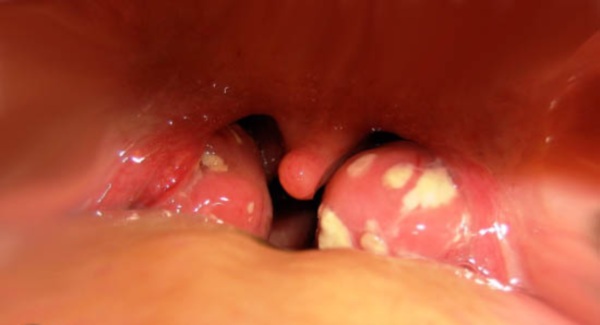

Одне з гострих бактеріальних запалень глоткових мигдалин носить назву фолікулярної ангіни. При цьому фолікули, які є нічим іншим як лімфатичними вузликами, видно при огляді горла – це «пупиришки», горбки, рідше прищики, або гнійники на мигдалинах.

Фолікули – скупчення лімфатичної тканини, з якої складається сама мигдалина. До запального процесу можуть залучатися інші мигдалини, при цьому прищі і гнійники білого кольору розміром з шпилькову головку будуть локалізуватися на задній стінці глотки.

Хвороба починається гострого головного болю, загальної інтоксикації, високої температури. Хвора людина скаржиться на горло — різкий біль, що посилюється при ковтанні. При огляді можна побачити гіперемійовану слизову, запалені мигдалини збільшені, бульбашки на горлі і мигдалинах, білі прищі, гнійники.

Білі пухирі в горлі: що це? Може бути фолікулярна ангіна. Це важке інфекційне захворювання, пов’язане із запаленням мигдаликів. Хвороба є наслідком переохолодження у людей зі слабким імунітетом.

Фолікули – щільні згустки лімфатичної тканини – запалюються і стають схожі на білі вузлики. Розмір їх зазвичай не перевищує величину сірникової голівки. На кінці такого вузлика може утворитися гнійник.

Спочатку фолікулярна ангіна може нагадувати кишкову інфекцію. Але досить широко відкрити рот і подивитися в дзеркало, щоб переконатися в помилковості діагнозу: білі пухирі на мигдалинах можна побачити неозброєним оком.

Фолікулярна ангіна є найважчою і небезпечною з усіх ангін. Її супроводжує запалення фолікул і регіонарний лімфаденіт. Основна причина хвороби – бактеріальна інфекція, яка зазвичай вражає людей з ослабленим імунітетом.

Під час захворювання фолікули сильно збільшуються в розмірах і стають схожими на пухирі, які легко помітити, якщо хворий широко відкриє рот.

Своїм виглядом фолікули нагадують маленьке зернятко, наповнене гнійним інфільтратом. Найчастіше хвороба має гострий перебіг, і обов’язково, а про її появу свідчать наступні симптоми:

- На мигдалинах можна спостерігати білий наліт і сильне почервоніння.

Найбільш яскравою особливістю захворювання можна назвати збільшення фолікулів у розмірах, це робить їх схожими на пухирі. Вони невеликі і спочатку білі. Потім колір їх змінюється, оскільки внутрішнє вміст перетворюється на гній. Хвороба вимагає обов’язкового лікування, оскільки вона прогресує дуже швидко і небезпечна ускладненнями.

Фолікулярна ангіна

Ця форма ангіни дуже поширене і частіше за все стосується людей до сорока років, інші менш схильні до хвороби. Піднебінні мигдалини сильно запалюються, опухають і червоніють, з’являються маленькі гнійні, розміром із зернятко, бульбашки в горлі. Вони можуть бути як жовтого, так і білого відтінку.

Якщо у пацієнта з’явилися білі пухирі в горлі, то це свідчить про виникнення фолікулярної ангіни. Ця хвороба відноситься до ускладненим формам ангіни і характеризується ураженням мигдаликів.

Тонзиліт проявляється по різноманітним причинам. Це може бути звичайне переохолодження, часті простудні хвороби, приєднання бактеріальної інфекції.Фолікули є щільними згустками лімфатичної тканини, яка запалюється і стає схожа на білуваті горбики. Розмір їх не перевищує більше двох міліметрів, а всередині розташовується гнійний вміст.

Такий вид ангіни є найбільш небезпечним, так як супроводжується запальним процесом в мигдалинах. Протягом цього захворювання фолікули, які являють собою невеликі лімфатичні вузли, виглядають як бульбашки.

Самі фолікули являють собою досить щільний згусток лімфатичної тканини, яка становить основу мигдалин. Запальний процес провокує появу на мигдалинах пухирів. Найчастіше подібне ураження носить гострий характер.

Фолікули є щільними згустками лімфатичної тканини, яка запалюється і стає схожа на білуваті горбики. Розмір їх не перевищує більше двох міліметрів, а всередині розташовується гнійний вміст.